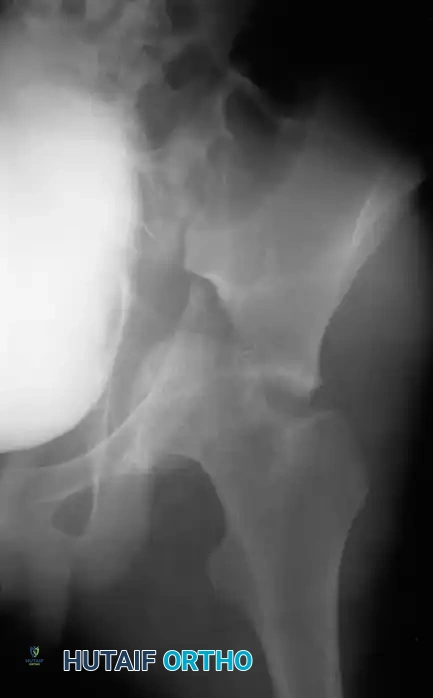

Fig. 53-3 Transverse acetabular fracture with true central fracture-dislocation; intrapelvic femoral head can become locked between superior and inferior fracture fragments.

In these scenarios, the femoral head may become incarcerated between the superior and inferior fracture fragments, rendering closed reduction impossible.

Fig. 53-4 Anteroposterior pelvic radiograph ( A ) and CT scan ( B ) of irreducible hip dislocation with posterior wall acetabular fracture. Posterior wall fragment is incarcerated, blocking reduction.

If closed reduction under conscious sedation or general anesthesia fails, urgent open reduction is mandated. A rapid, fine-cut (2-3 mm) Computed Tomography (CT) scan should be obtained to identify the incarcerating fragment—often a rotated posterior wall fragment or an intra-articular osteochondral loose body. Prolonged dislocation exponentially increases the risk of femoral head osteonecrosis and irreversible sciatic nerve ischemia.